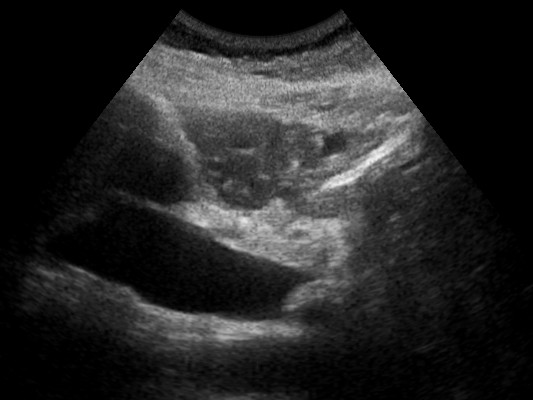

Tanto durante os testes, quanto nas diversas ultrassonografias feitas durante os 9 meses de gravidez, a gestação parecia estar ocorrendo bem, e Ada estava crescendo perfeitamente na barriga da futura mamãe; o que ela não podia esperar, porém, era a chegada de um segundo bebê dois minutos depois de ter dado à luz a Ada...

A própria Lyndsay relata aquele momento absurdo agora com estas palavras surpresas: "Lembro-me de quando estava dando à luz, eles usaram um monitor e se ouvia o batimento cardíaco de outro bebê. Todos na sala estavam sem palavras. Nenhum de nós sabia como processar isso. Aquilo estava acontecendo. Acho que meu rosto diz tudo!"